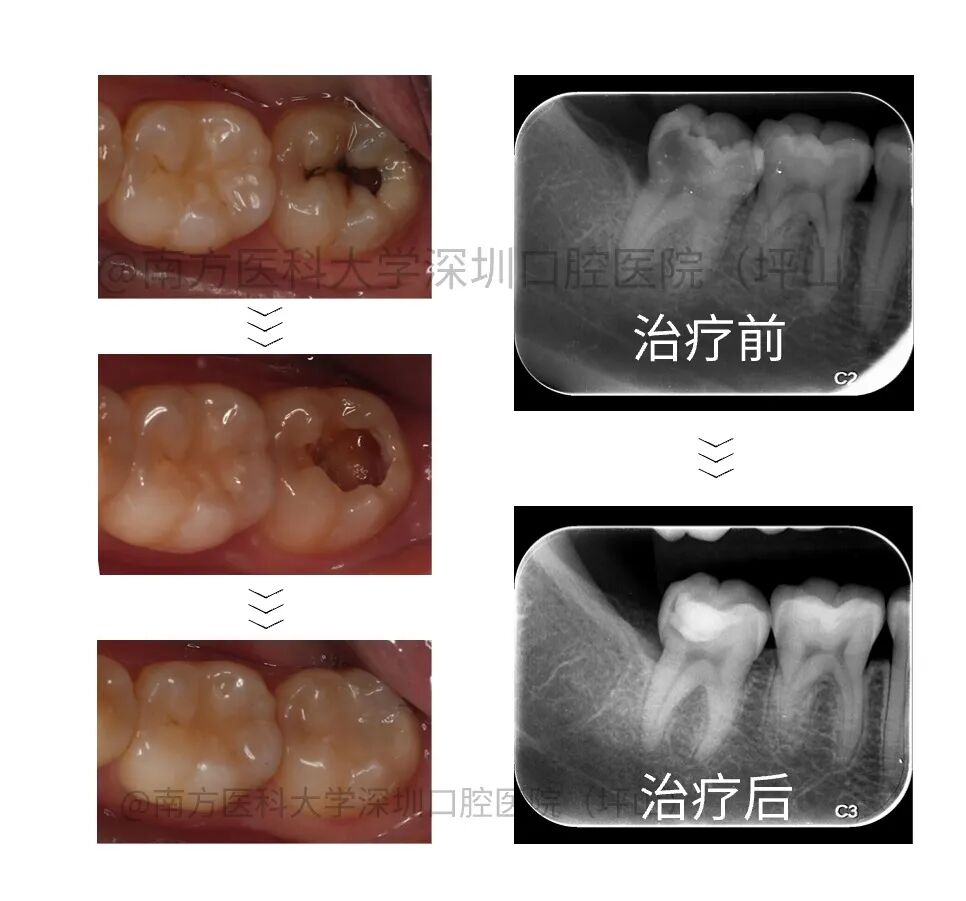

案例三

患者自诉左下后牙有洞,冷热刺激痛数月,影像检查显示 36 牙𬌗面深龋近髓,根尖未见异常。建议试行活髓保存治疗。一年后复查无异常。